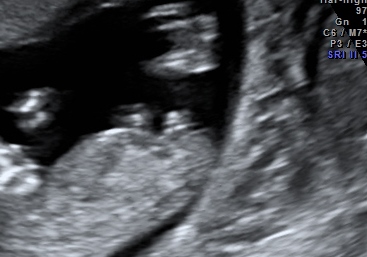

The tech would not say anything about the nub! I see two flat lines and behind it i think is the cord. She did say the cord was next to the legs. Help!!Attachment 17385Attachment 17386

the 2 lines are straight and they are parallel and could mean girl. Although the 2 lines are spread really far apart.

The question is...what is that blob ontop?? Is that blob attached to the top line?? If so, then boy. If its the umbilical cord or whatever floating on top then its clearly a girl.

The problem is no one knows the answer to those questions and if those are the only 2 pics you have then we are at a loss here for guesses.

the more i zoom in and look at it -- I don't think that blob is attached.

Thats just my thought though - I think its a girl and that's just part of the umbilical cord and unfortunately its positioning is REALLY bad for nub guessing and its gonna freak you out.

If I had to guess, its a girl and you got stuck with an unfortunate u/s pic.